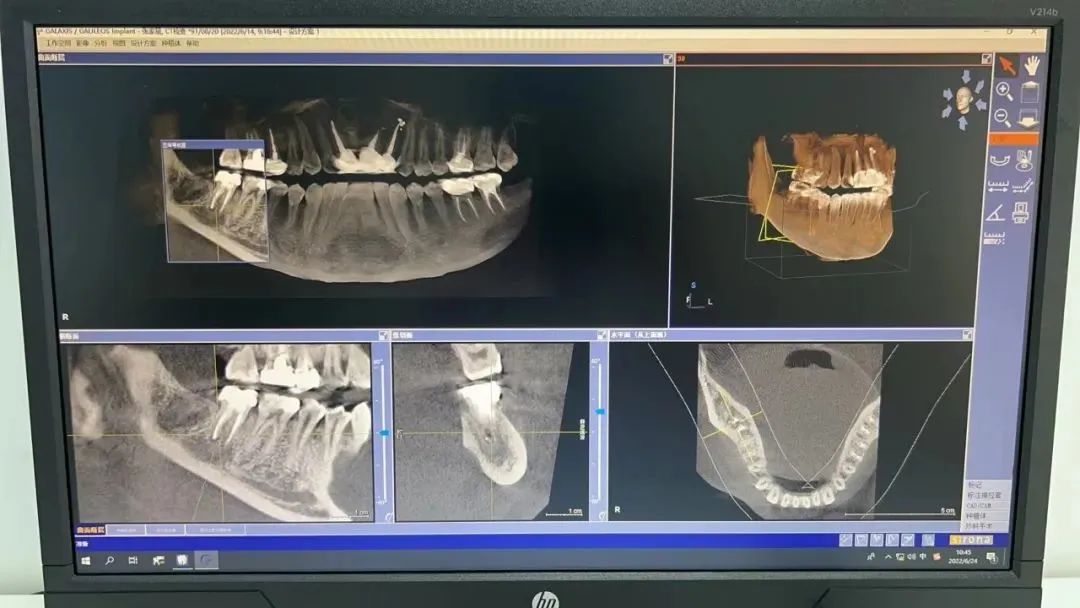

近日,洛阳市第三人民医院口腔颌面外科引进了意大利NEWTOM品牌的口腔锥形束CBCT机,该设备是目前牙科影像设备中的高端CT机,它集三维立体检查、全景扫描、远距离X射线扫描(头影测量)、连续动态X射线扫描多功能于一体,它的投入使用,标志着我院口腔颌面外科将为市民带来更精准、更安全的口腔健康服务。

据了解,口腔CBCT相较于牙片机、全景机等传统产品,CBCT在分辨率、失真率等参数方面要远远占优,可以大幅降低诊断误差,具备数字化口腔扫描的显著优势。与传统CT相比,CBCT主要具有以下优点:

1、提高种植牙的准确率:系统的分析口腔颌面部的数据,配合软件,在计算机上制定精确的种植计划,精准的进行种植术前诊断与设计以及种植术后评估,使医生与病人承担的风险大大降低。

3、为牙体牙髓病及牙周病的检查提供了丰富而准确的细节信息,能很好的显示根管解剖结构、根尖周骨质情况及牙槽骨缺损的位置和程度。清晰显示根管走向、形态和数量。对于多根管和复杂根管的病例,可以通过直观的三维演示从任意角度更精确观察。

4、精准定位:可以直观的发现口腔颌面部囊肿,并显示病变区域的大小、内部骨质变化以及病变区与周围解剖组织的位置关系,对于诊断、治疗方案设计具有重要意义。

5、降低拔牙风险:可准确显示多生牙、阻生牙的形态、方向、与邻牙及临近重要解剖结构的位置关系,方便医生更为准确的制定治疗方案、评估手术风险及预后。

CBCT可广泛应用于口腔各个领域,除了种植和正畸业务,还可延伸到口腔颌面外科、牙体牙髓病、牙周病、颞下颌关节疾病等细分领域。通过CBCT的引进,我院口腔颌面外科在口腔疾病防治及治疗水平将得到进一步提升,同时能更好地为广大患者的口腔健康保健护航。